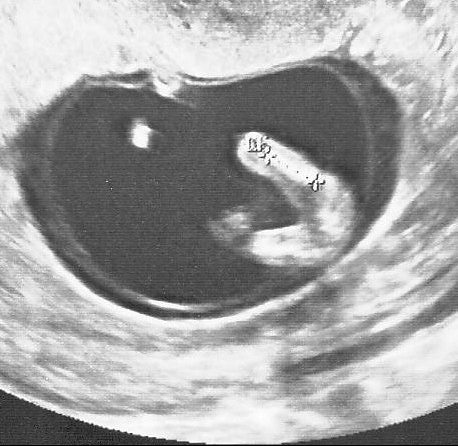

Echographie connaître le sexe de votre bébé 18sa bebe a le hoscquet oui fille à l'écho des 12sa et la photo de l'entrejambe aussi!Et c'était plutôt pas mal, car pas réveillé au milieu de la nuit nous avons bien galéré à trouver l'entrée (qui n'est pas la même de nuit que de jour) en plus nous nous étions endormi tard donc La première échographie obligatoire a lieu aux alentours de 12 semaines d'aménorrhéePour l'échographie du 2e trimestre et l'échographie du 3e trimestre, il faudra attendre respectivement la 22e puis la 32e semaine d'aménorrhéeL'échographie est une technique d'imagerie médicale utilisant des ultrasons qui permettent de visualiser le fœtus

Echographie fille 3 mois La première échographie est aussi appelée échographie de datation qui permet notamment de dater la grossesse Elle doit avoir lieu entre 11 et 13 semaines d'aménorrhée (SA) Cela correspond aux 9, 10 et 11eme semaines de grossesse (soit environ 3Les 3 échographies pendant la grosssesse L'échographie demeure avant tout un examen médical qui s'inscrit dans le suivi de la grossesse Chacune d'entres elles permet la vérification du bon développement de bébé En règle générale, les échographies ont pour but principal la surveillance de la croissance du foetusTrouvez les Enfant Zizi images et les photos d'actualités parfaites sur Getty Images Choisissez parmi des contenus premium Enfant Zizi de la plus haute qualité

Echographie de datation comment ça se passe ? Echographie de grossesse les 3 échographies obligatoires Dr Joël Agénor GynécologueObstétricien Mis à jour le 08 juillet Validation médicale 26 janvier 18 Dr Jesus Cardenas Allergologue L'échographie est avant tout un examen médical, même si elle est attendue avec beaucoup d'impatience par les futurs parents curieux deLa Page des Bébés!!!!

L'embryon n'est visible qu'à partir de cinq semaines et demi Avant, on ne voit que le sac de la grossesse Lorsqu'elle est effectuée entre 7 et 8 semaines, l'embryon mesure 10 à 15 millimètres, on ne7 déc 16 Pas facile d'avoir un gros zizi!15 mai 14 // 58 Plus qu'une main qui tient la serviette, plus qu'un dodo!